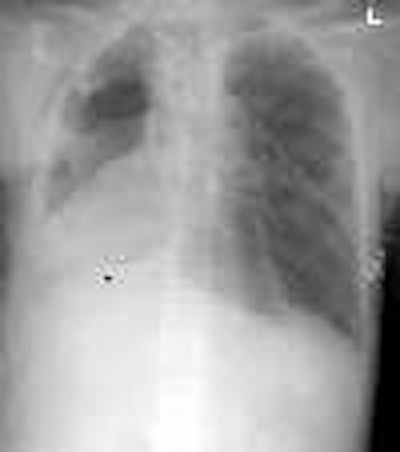

Torsio1aThe patient had a known central right lower lung bronchogenic carcinoma. He presented with massive hemoptysis. The admission chest radiograph demonstrated dense consolidation and volume loss within the right lower lung.